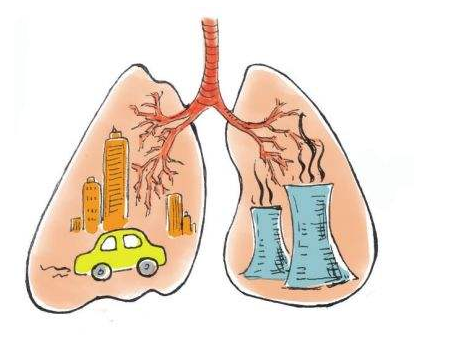

粉塵是一種重要職業危害因素,有人視之為洪水猛獸,也有人對其知之甚少。對於粉塵你了解嗎?它來源於哪裏?對健康有何影響?茄子AV网站該如何防護?[粉塵淨化器]

粉塵是能長期漂浮在空氣中的顆粒物,往往產生於生產過程中,它不僅照成環境汙染,最重要的是會損害勞動者健康,可引起塵肺等內在的多種職業性肺病,因此粉塵防護是職業健康保護中的重中之重。[粉塵茄子视频懂你的更多] 您的工作環境中有粉塵嗎?以下生產性粉塵存在於眾多行業及崗位中,比較廣為人知的有:

粉塵主要經過呼吸道進入人體,可經過鼻腔、咽喉、支氣管最終到達肺泡,當然,人體並不會讓這些小顆粒任意妄為,機體通過各種清除作用,可排出,進入呼吸道的97%~99%的粉塵大概會有約1%~3%的粉塵沉積在體內,然而,如果長期吸入粉塵可消弱機體清除功能,導致粉塵過量沉積,對健康造成不良影響。[吸煙係統]

總體來說,粉塵對健康的損害是多方麵的,主要以呼吸係統為主,包括以下幾種健康隱患: